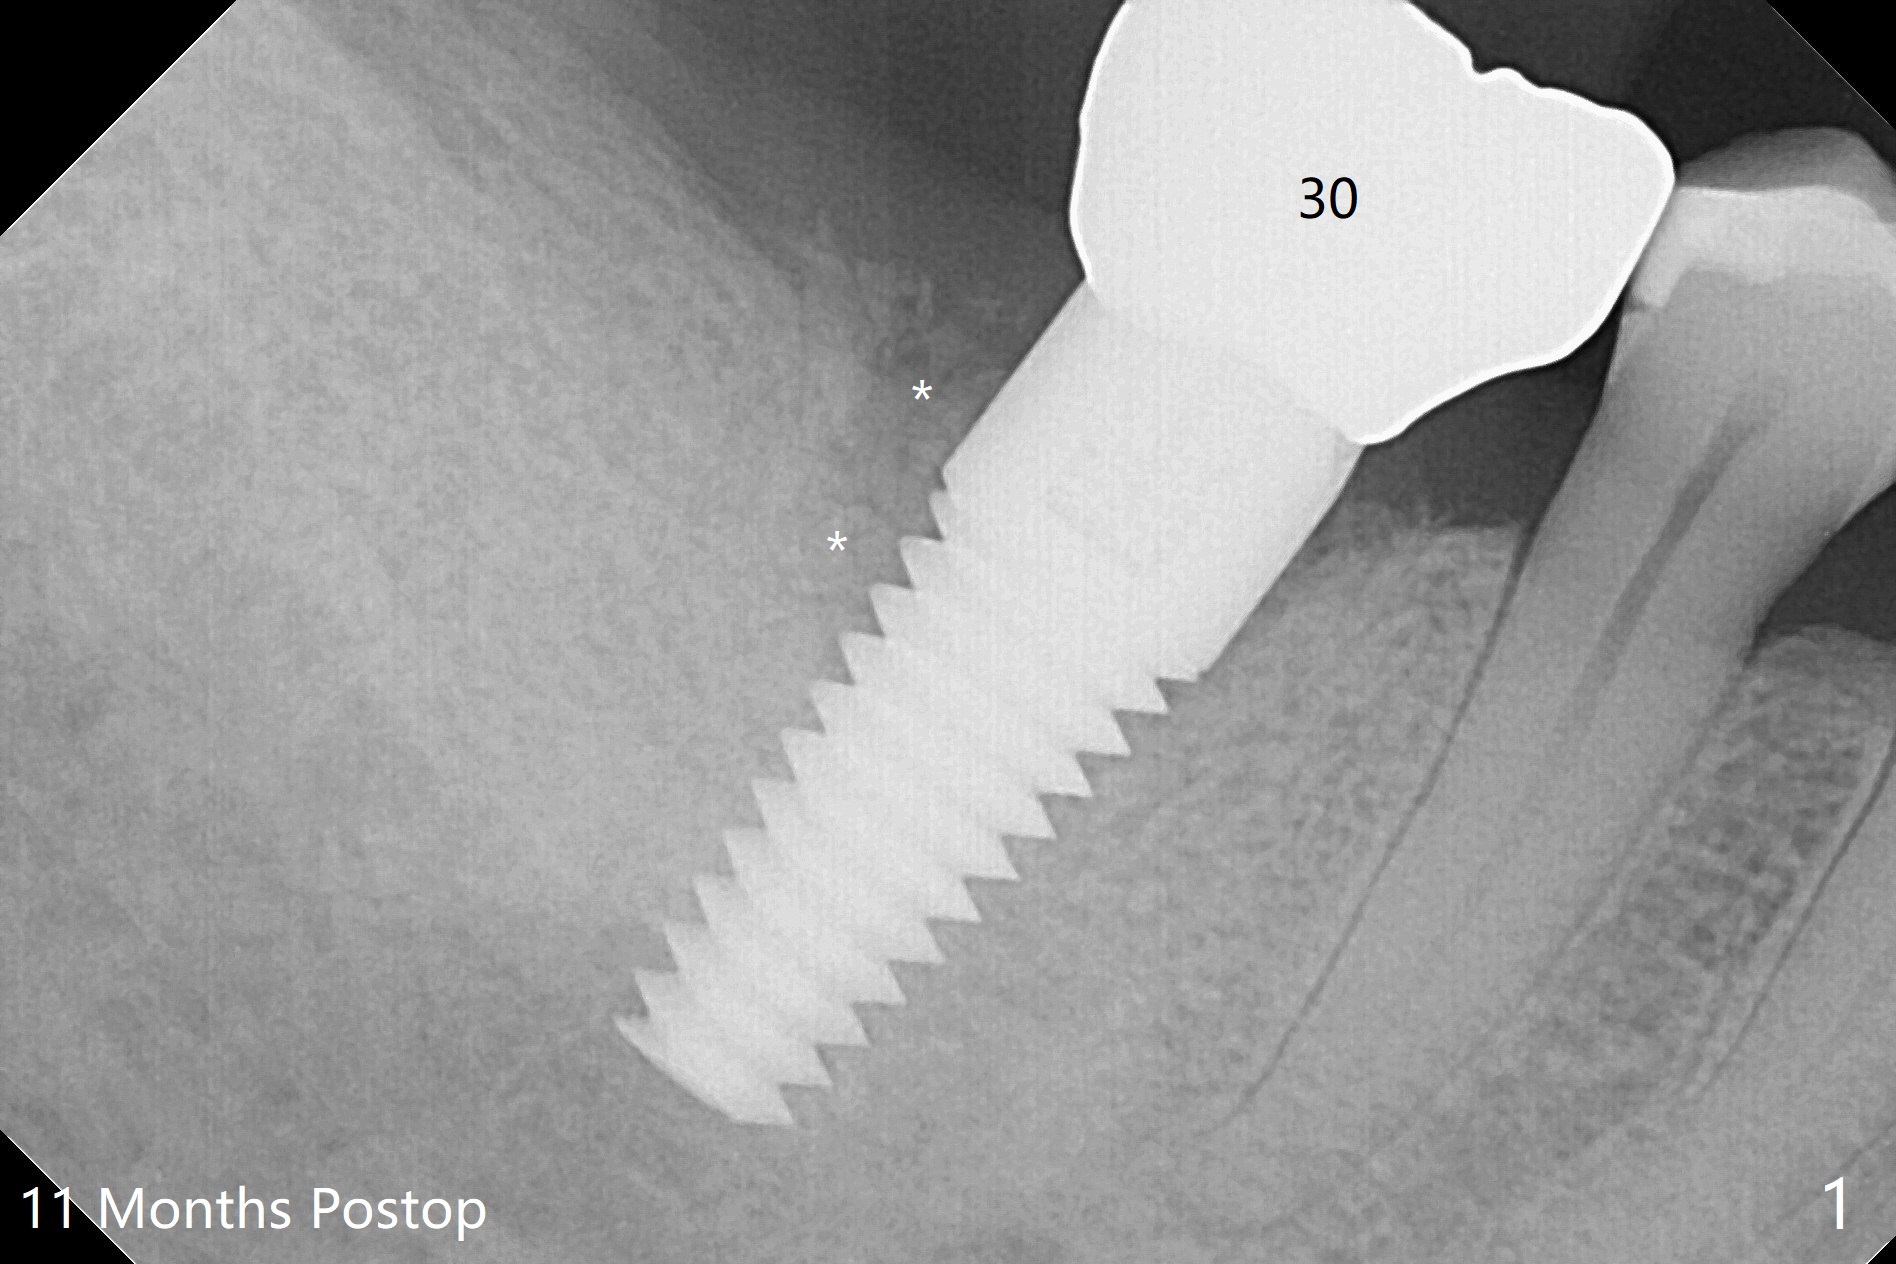

There are signs of periimplantitis at #30 eleven months postop (Fig.1 (* bone loss)). The bony defect (Fig.2) will be filled with allograft mixed PRF liquid to form sticky bone (Fig.3,4), followed by PRF membrane (not shown) and a piece of 6-month membrane (Fig.5). A hole is cut so that the 6-month membrane can slide down the abutment (Fig.2,5 A) to cover the bone graft around the implant (Fig.2,7 I). Setting acrylic is applied around the abutment and neighboring teeth for further protection and holding (Fig.8). The periimplantitis does not resolve nearly 7 months post graft. The implant will be removed. Prepare UF extra wide kit and try to insert 6.5 or 7.0 mm tap. Also prepare sticky bone and Cytoplast for wound closure. Implant removal involves surgical handpiece, 6.2/7 mm trephine bur, elevators, and implant driver. The defect is large (Fig.9) with the low buccal crest (Fig.10) and bone graft with PRF ("sticky bone") is placed, covered by PRF and 6-months membrane (Fig.11). The next implant will be placed with guide. If oral hygiene is not ideal, choose a bone level implant. The middle of the wound dehiscences slightly 8 days postop (Fig.12), accounting for mild loss of bone graft 1 year postop (Fig.14). The keratinized gingiva is apparently wide 1 year postop (Fig.13). There is mild loss of bone graft in the middle of the superficial area (Fig.14). The buccal plate seems to regenerate 1 year postop (pandemic delay, Fig.15).